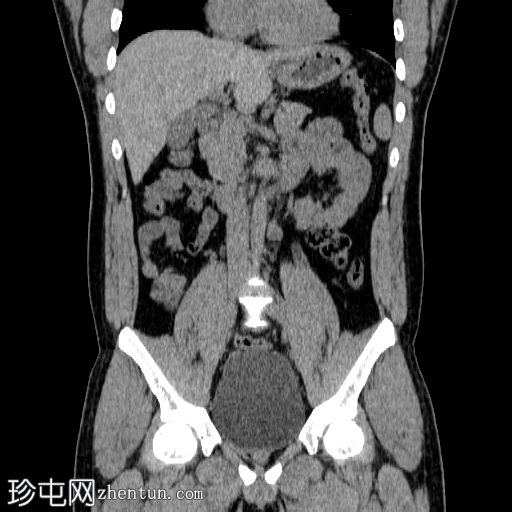

冠状位

平扫

双侧肾结石,无梗阻,较大结石位于左侧肾下盏,最大直径约4 mm,平均CT值约730 HU,伴左侧输尿管轻度扩张。

膀胱明显充盈,高度达脐部,若患者无法排尿,可能需要导尿。

患者主诉左侧肾绞痛,既往有肾结石病史。